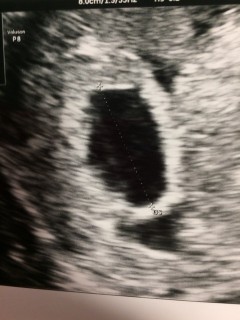

2人目の妊娠です!1人目の時は7w5dで初めて心拍確認できました! 今回は早く確認できて嬉しくて(^ω^) 元気に育ってね。 まだ3㎜で予定日わからず、2週間後もう一度検診です